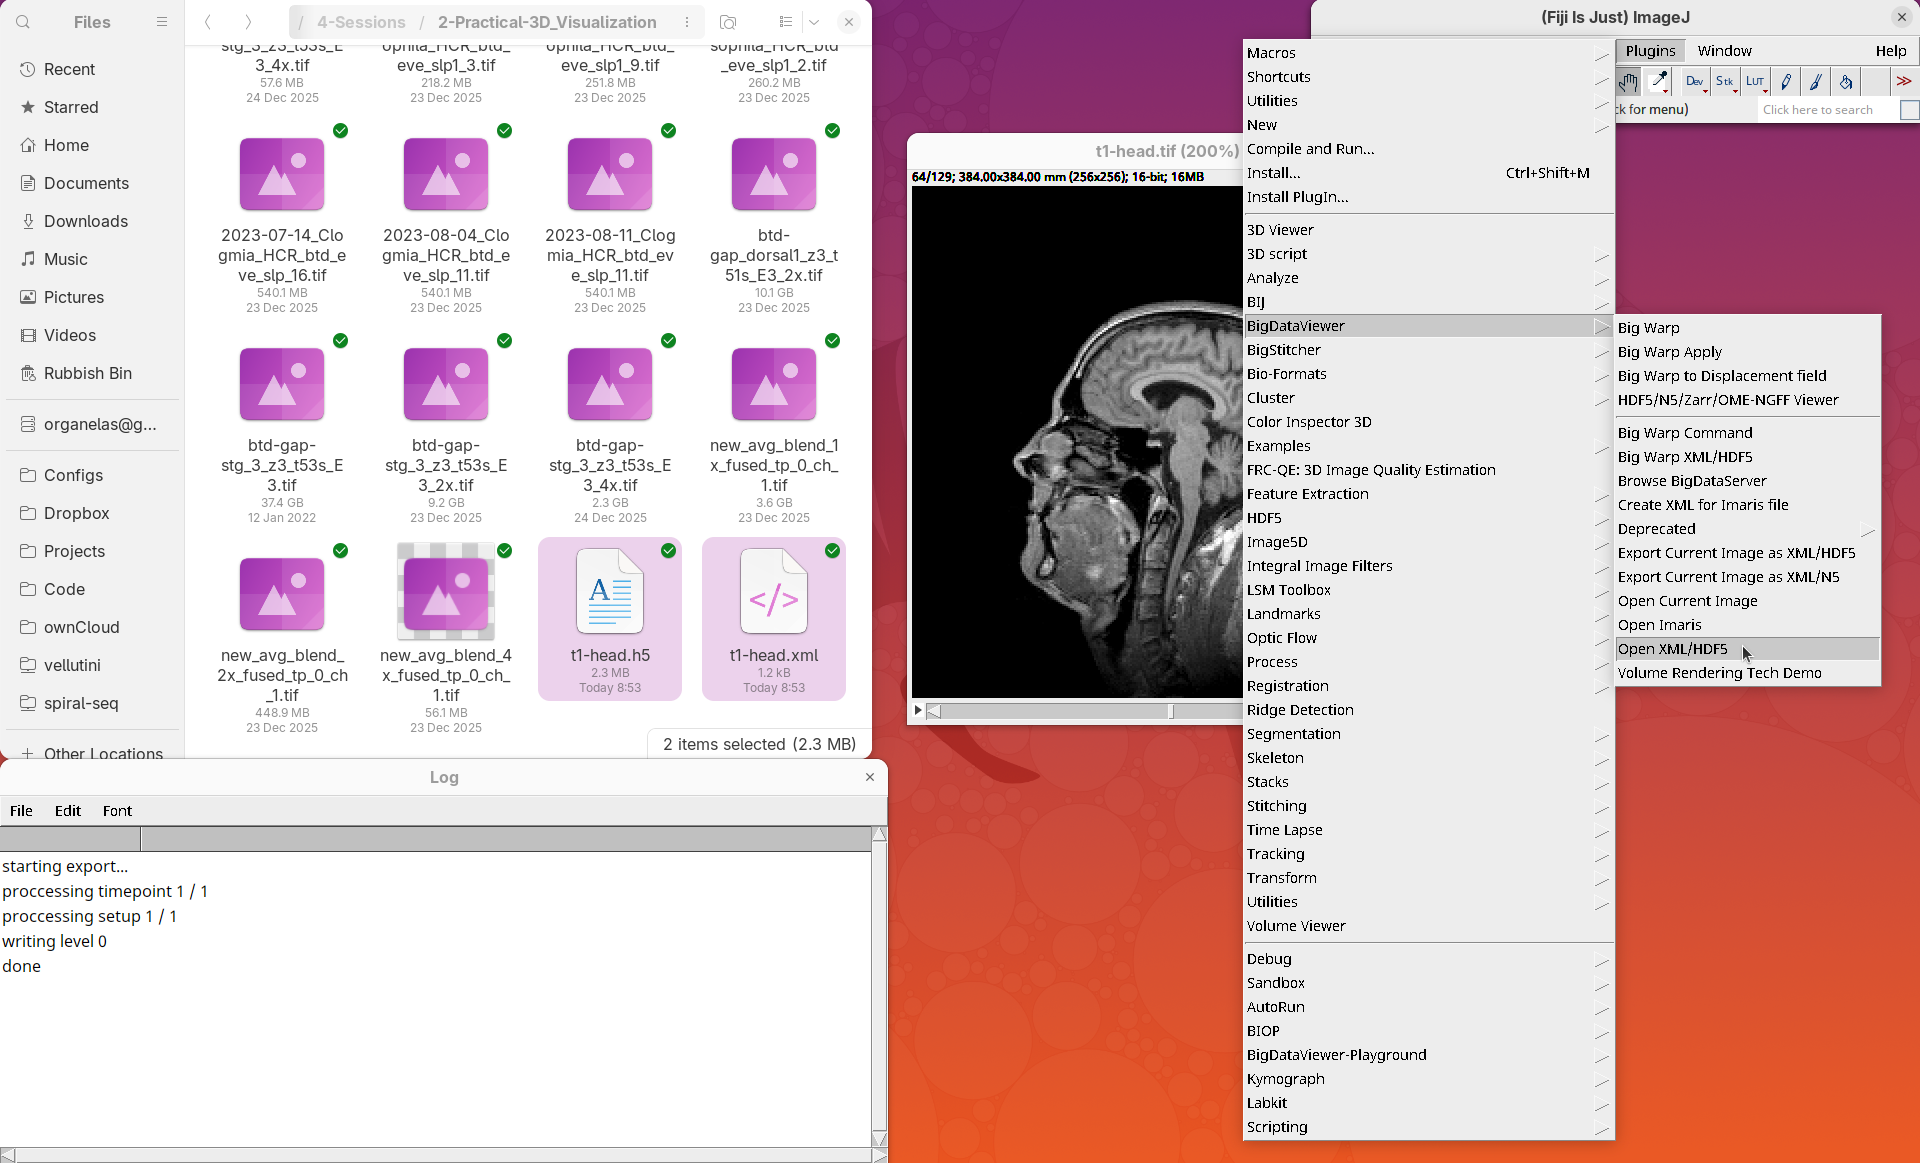

BigDataViewer

BigDataViewer (Pietzsch et al. 2015) is one of the most important tools for visualizing large, multidimensional datasets. It provides a simple and intuitive interface and shortcuts to swiftly navigate through your sample even on a regular laptop. This is possible because of the underlying file format used by BigDataViewer: the XML/HDF5 combo. Therefore, before opening the plugin, we must convert our dataset.

- Go to

Plugins>BigDataViewer>Export Current Image as XML/HDF5.

A dialog with export options will open.

- Under

Export path, click onBrowseto select the output directory fort1-head.xml.

The export process will start. Since this is a small dataset, it’ll be fast. But, for large datasets, this can take hours.

When done, you will find two new files in your working directory: t1-head.xml and t1-head.h5.

The XML file stores metadata information about the image. The HDF5 file stores actual image data. These two files will always be in a pair. To open the XML/HDF5:

- Go to

Plugins>BigDataViewer>Open XML/HDF5and select thet1-head.xml.

The BigDataViewer interface will open showing an optical section of the head sample.

Getting familiar with BigDataViewer is an essential skill for navigating large 3D datasets. It’ll also be important for the multiview registration pipeline. So, take the time to learn the basic commands and shortcuts. It is nicely intuitive. The BigDataViewer’s page on the ImageJ Docs has the official documentation and we can also go to Help > Show Help for an up-to-date overview.